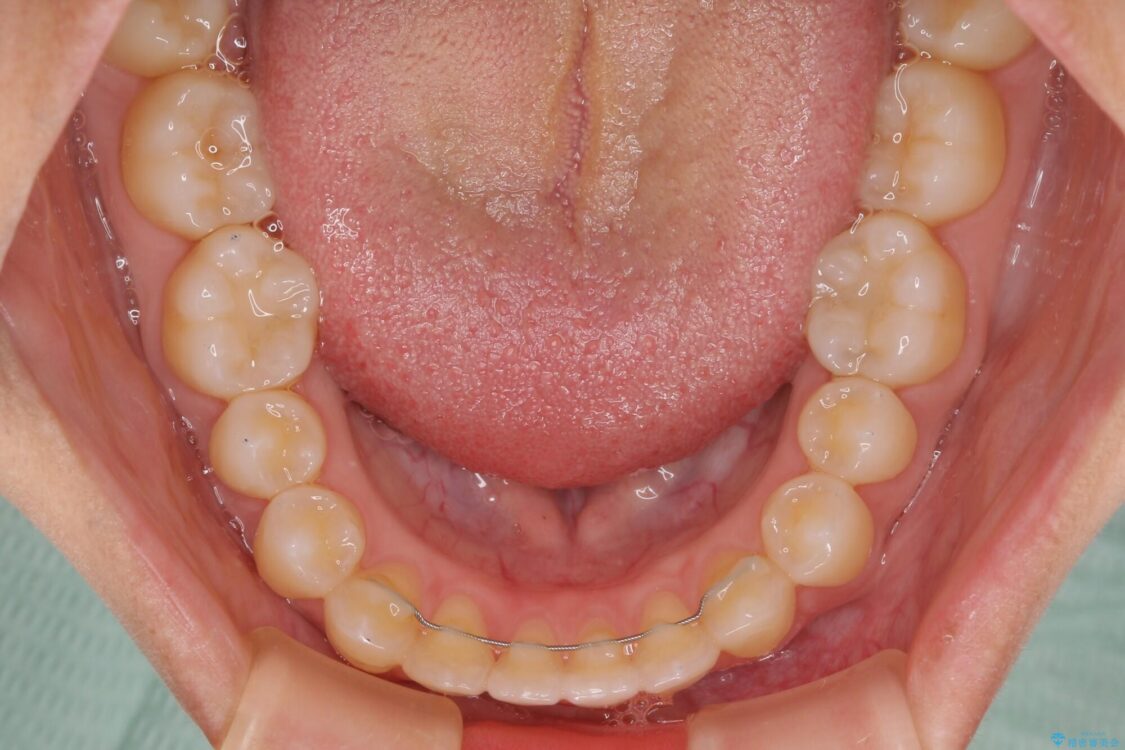

空隙歯列(すきっ歯)は、舌の突出癖をある程度改善できたとしても、後戻りにより隙間が開きやすいと言われています。

裏側から細いワイヤーで保定するとともに、睡眠時のマウスピース装着を徹底していただくことで、後戻りを最小限にとどめます。

治療後

• 隙間だらけの歯列 インビザラインで改善 治療後画像